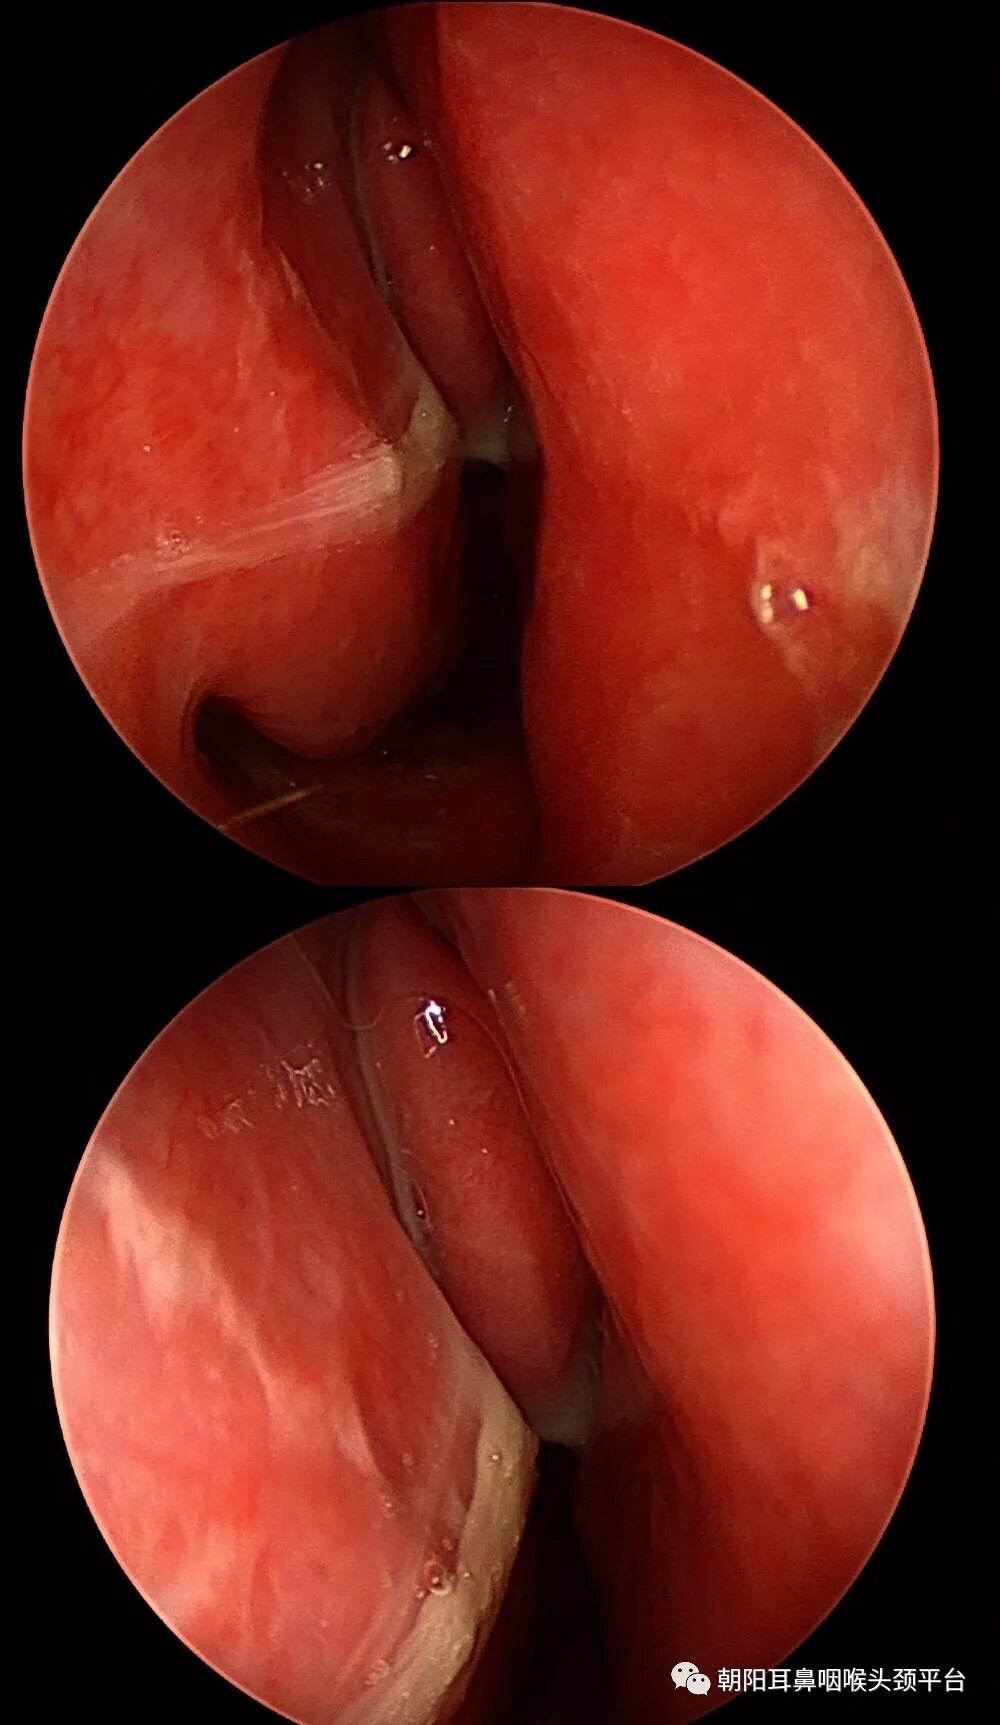

鼻内窥镜一种耳鼻喉科设备,是一种能对鼻腔进行详细检查的光学设备,一般指的是硬管镜,有0至90度不等的

目前鼻内窥镜导光性强、多角度、视野大,可直接窥视到鼻腔内的各个重要部位及鼻咽部的细微病变,因此在选择

鼻内镜是硬性内镜,带有光线充足的冷光源,通过镜像放大,能深入鼻腔清晰目前临床上常用的内镜为0°、30°

鼻内镜手术,操作方法步骤,图片图解,手术图谱,鼻部手术,手术治疗实例,鼻使鼻腔、鼻窦,尤其是深部的手术能